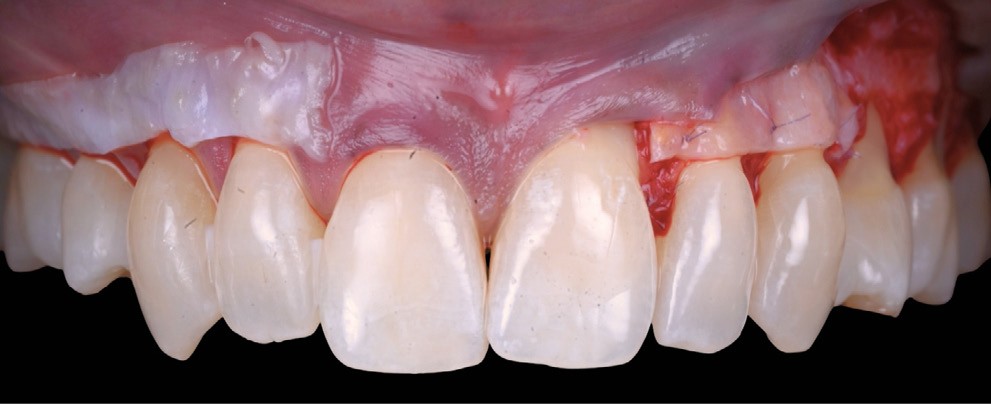

Une chirurgie combinée est réalisée (fig. 4) :

- tunnélisation secteur 1, élévation d’un lambeau secteur 2 ;

- prélèvement épithélio-conjonctif unilatéral au palais, désépithélialisé et divisé en deux ;

- greffon de lamina propria inséré dans le tunnel (secteur 1) et suturé au périoste (secteur 2) ;

- jeu de sutures au fil 6.0 : « double cross » en fils non résorbables secteur 1 / « suspendues » en fils résorbables secteur 2.